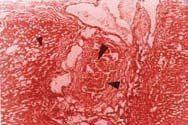

Histológicamente los cortes de los ratones sacrificados el día 1 (24 horas postobstrucción), mostraron congestión sinusoidal y vascular a nivel de los vasos portales con estasis biliar asociada en 20% de los cortes. Estas lesiones se consideraron como leves (figuras 1a, 1b). Los cortes obtenidos el día 7 mostraron acumulación de pigmento biliar en colangiolos y zona pericolangiolar, con proliferación portal de colágeno en 60% de los cortes. Estas lesiones sumadas a las consideradas leves, se refieren como lesiones moderadas (figuras 1c, 1d). En los cortes de los tejidos de los ratones sacrificados el día 15 postobstrucción, además de las lesiones observadas en los días 1 y 7, se encontró proliferación hamartomatosa de colangiolos y fibrosis portal en conductos biliares, placa limitante y lóbulos en 15% de los cortes. Estas lesiones se clasificaron como severas (figuras 2a, 2b, 2c, 2d). Las lesiones observadas a nivel de cerebro, corazón y pulmones se debieron a congestión vascular y dilatación en varios grados. Los riñones mostraron precipitación de pigmento biliar en los túbulos colectores al día 15 de sacrificio. El grupo control presentó morfología macroscópica y microscópica hepática normal.

Figura 2a. Trombosis biliar colangiolar (flecha grande) asociada con fibrosis irregular incrementada en área portal y que envuelve al lóbulo (flecha pequeña), principalmente en centro.

Figura 2b. Trombo biliar intracolangiolar (flecha grande) con fibrosis periductal (flecha mediana) y proliferación colangiolar (flecha pequeña).

Figura 2c. Fibrosis portal e invasión lobular (flecha pequeña) y proliferación colangiolar (flecha grande).

Figura 2d. Proliferación colangiolar seudohamartomatosa a nivel portal (zona de flechas).